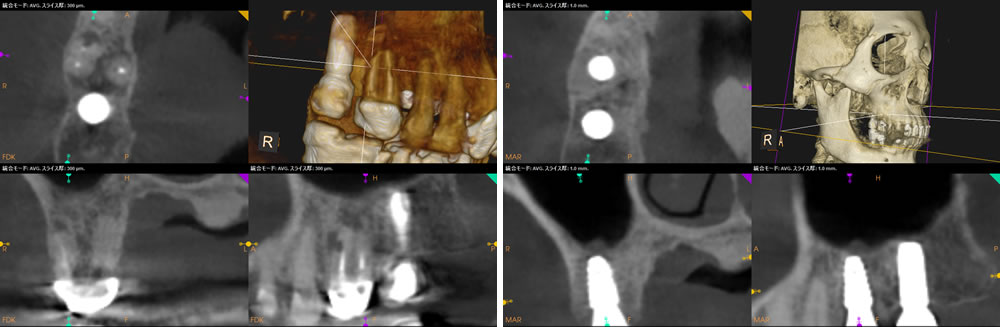

患者さまの「できるだけ体への負担を少なくしたい」というご希望を踏まえ、抜歯と同時にインプラントを埋入する抜歯即時埋入法で治療を行う計画を立てました。

まず、残っていた歯根を丁寧に抜歯し、計画に沿ってインプラントを適切な位置に埋入しました。抜歯後に生じた骨の欠損部には、ソケットリフト(上顎洞挙上術)を行い、インプラントの埋入と同時に骨を補う骨造成も実施しました。